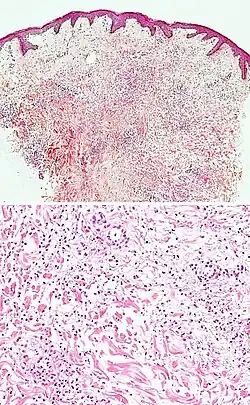

| Urticaria, lymphocyte predominant | Perivascular location. Mast cells are relatively sparse, potentially demonstrated with special stains, preferably tryptase stain. Extravasated erythrocytes are present in about 50% of the cases. No vasculitis.[14] | Dermal edema [solid arrows in (A,B)] and a sparse superficial predominantly perivascular and interstitial infiltrate of lymphocytes and eosinophils without signs of vasculitis (dashed arrow).[15]

| Urticaria, lymphocyte predominant | Perivascular location. Mast cells are relatively sparse, potentially demonstrated with special stains, preferably tryptase stain. Extravasated erythrocytes are present in about 50% of the cases. No vasculitis.[14] | Dermal edema (solid arrows) and a sparse superficial predominantly perivascular and interstitial infiltrate of lymphocytes and eosinophils (dashed arrow)

| Prevesicular stage of bullous pemphigoid | Image at right shows influx of inflammatory cells including eosinophils and neutrophils in the dermis (solid arrow) and blister cavity (dashed arrows), and deposition of fibrin (asterisks).[15] However, the diagnosis of bullous pemphigoid consist of at least 2 positive results out of 3 criteria:[19]

|